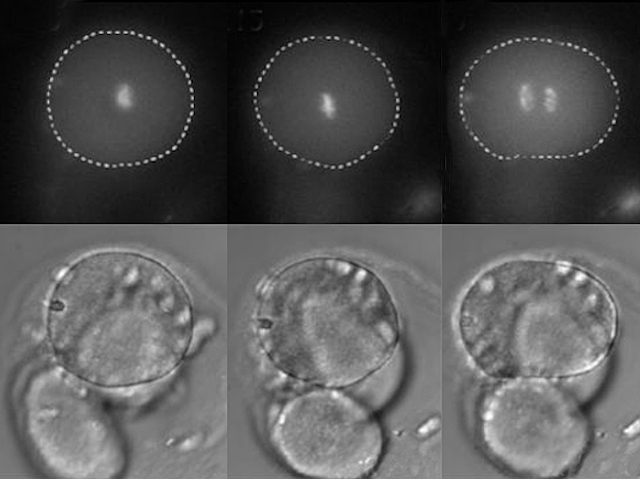

We all make mistakes in our lives. But making mistakes at the very earliest stages of life, when an embryo is just a few cells, can have a devastating impact. Problems with cell division during these crucial first days can lead to embryo cells ending up with the wrong amount of genetic material (chromosomes), leading to infertility, miscarriage or birth defects. To understand more about what’s going on, researchers have developed a technique to spy on these very early cell divisions in human embryos donated by women undergoing fertility treatment. They’ve discovered that the first cell division, when a fertilised egg splits from one cell into two (shown here), can take several hours to complete and often goes wrong. However, the second division from two cells to four is much more accurate, suggesting that getting the very first cell division right is probably the most crucial moment of our lives.